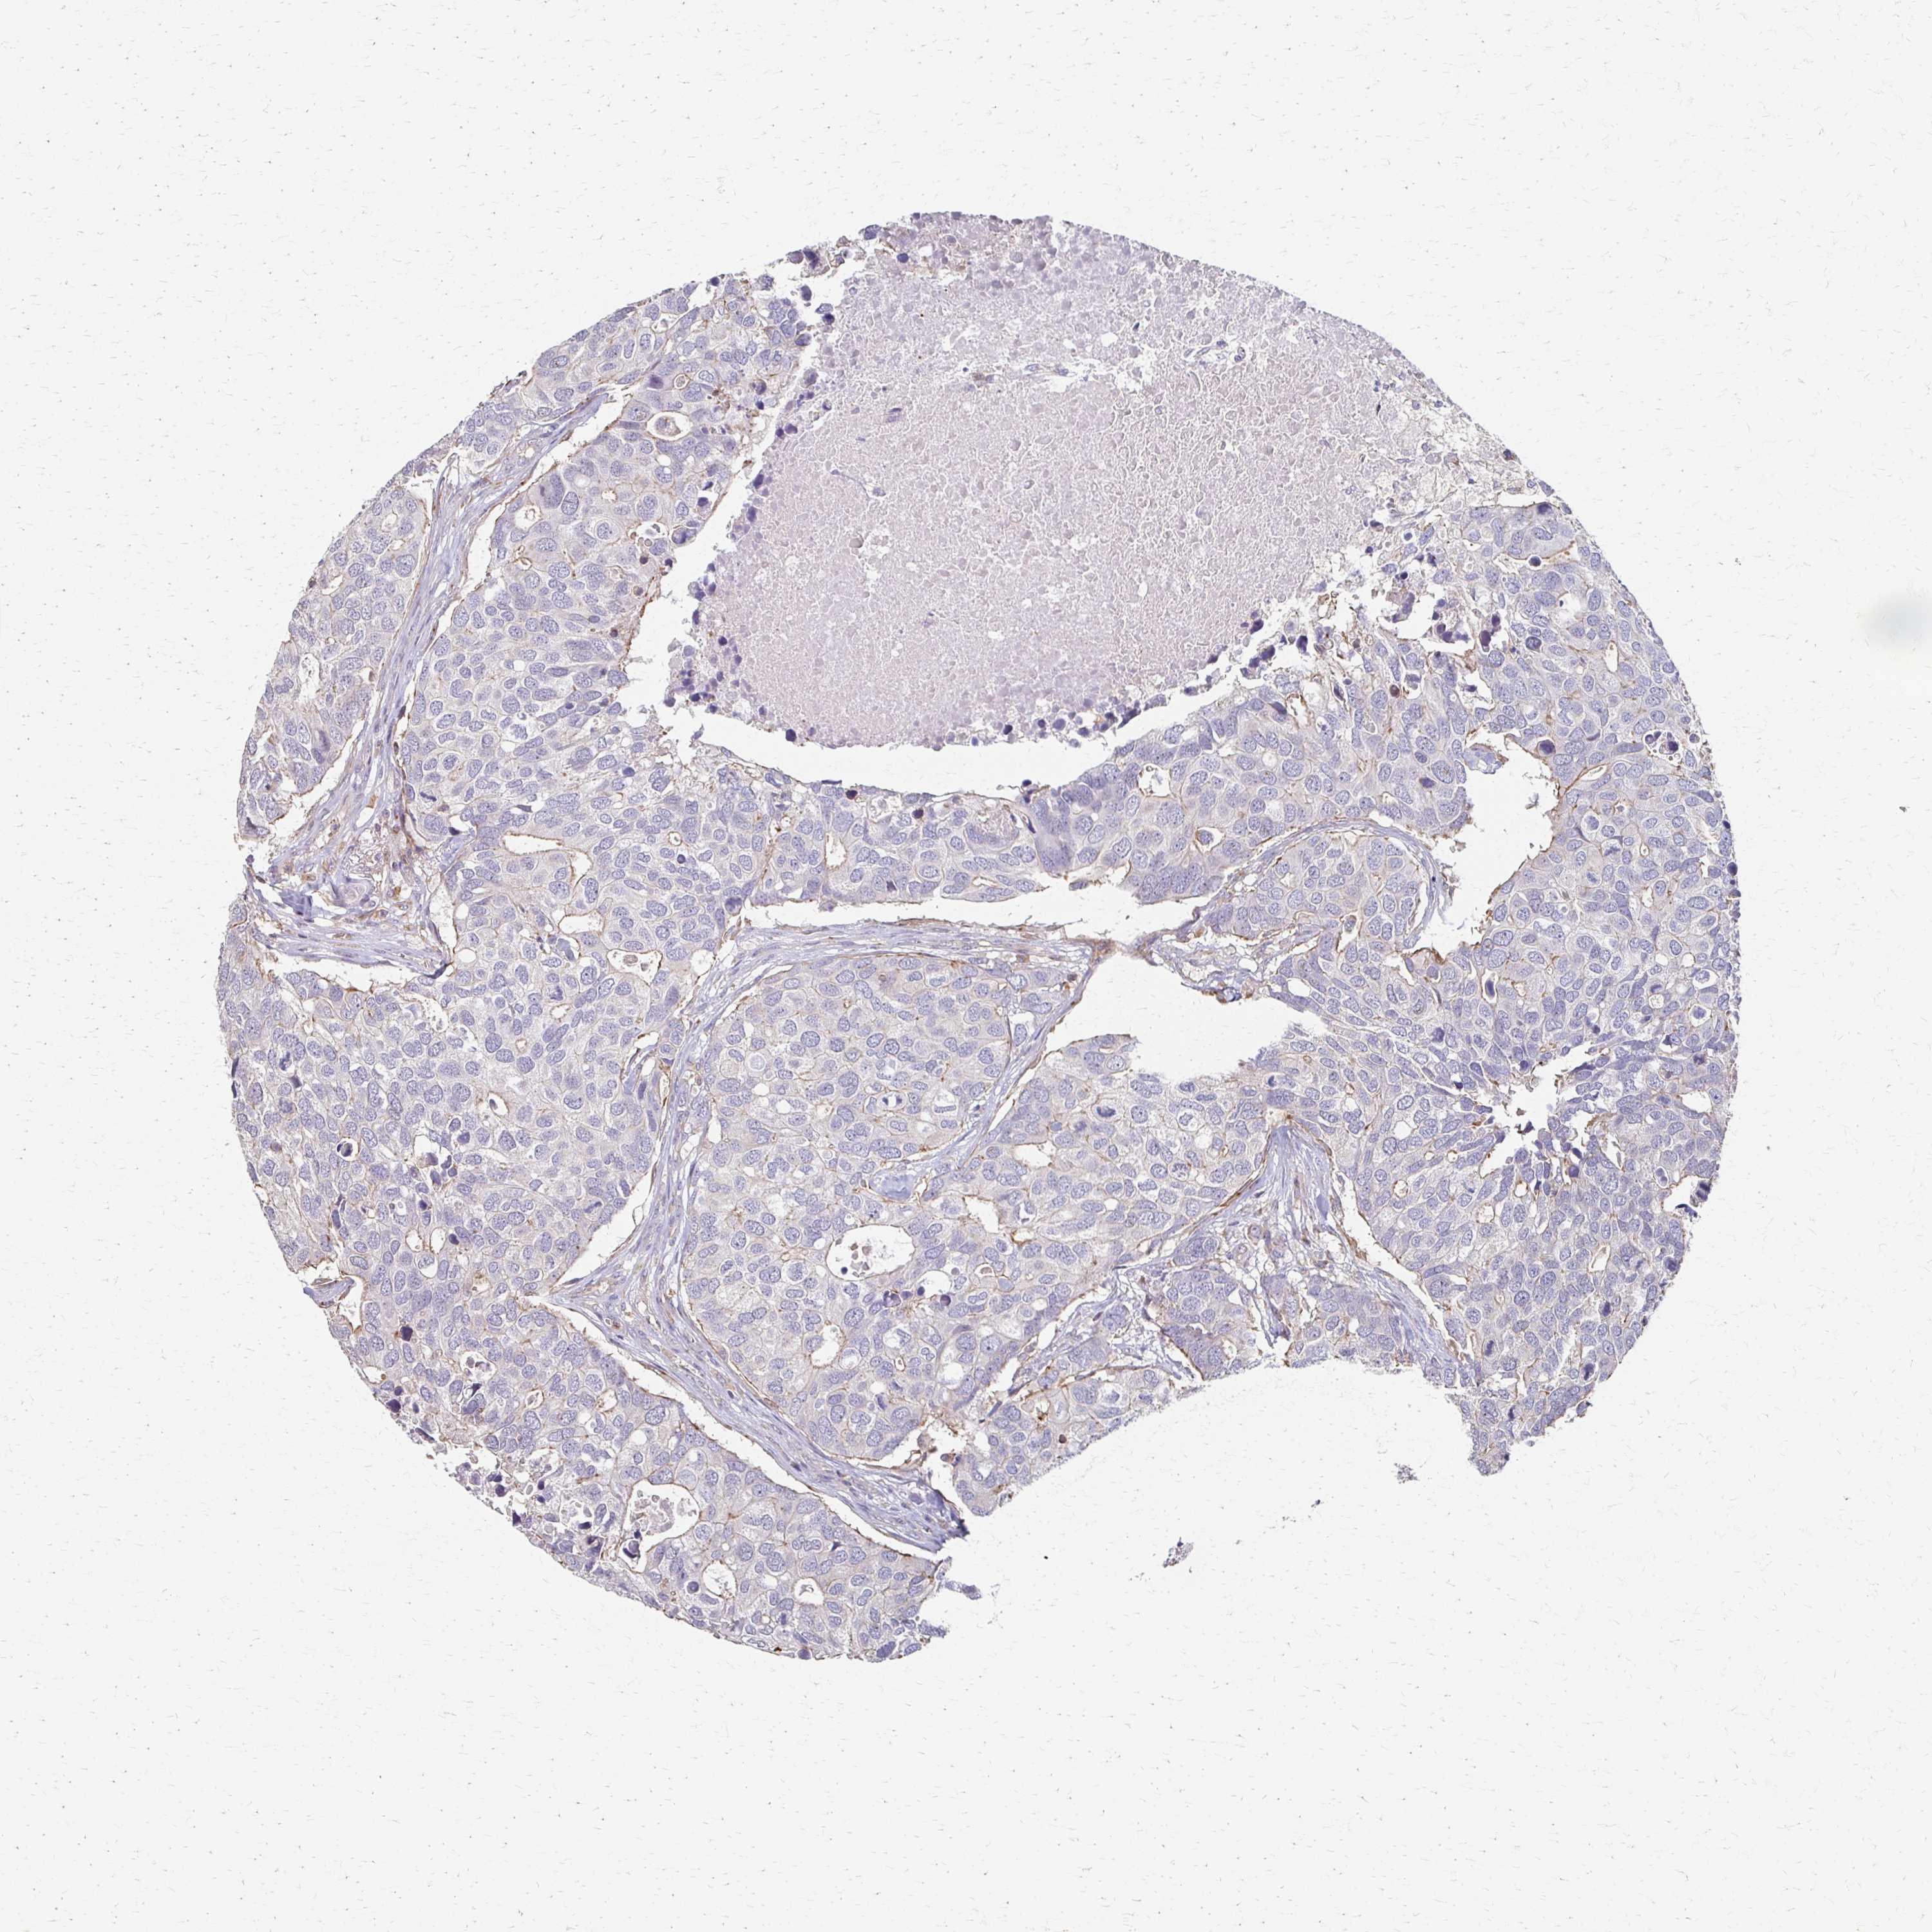

BRCA TCGA BRCA VALIDATION PROTEIN EXPRESSION

ANTIBODIES

AND

VALIDATION